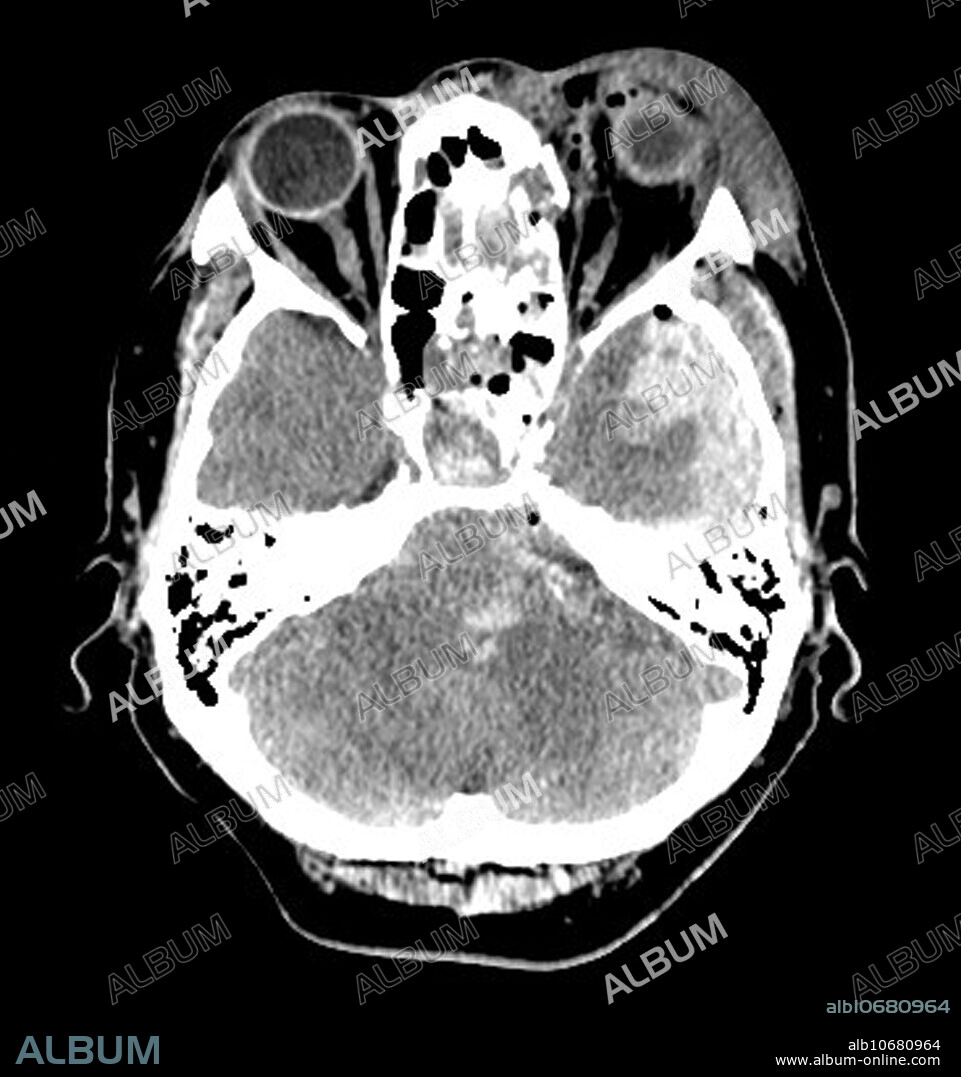

Title: Extensive Traumatic Brain Injury CT

Caption: This axial (cross sectional) CT image through the level of the orbits (eyes) shows severe soft tissue swelling/hematoma formation surrounding the eye on the viewers right. The sphenoid sinus is opacified with blood (white density) due to skull base fractures in the central part of the image. There is a subdural hematoma adjacent to the temporal lobe on viewers right in addition to temporal lobe contusions (hemorrhage-look white). Duret haemorrhages in the brainstem are seen.